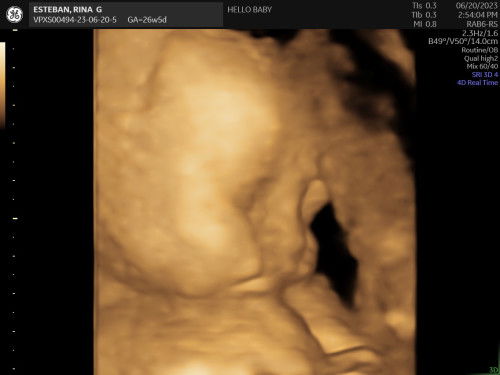

mga mami sino dito kinakabahan at the same time excited na lumabas si baby? konting kembot nalang talaga, eto na yun 3rd trim na!!!! sa tingin nyo ba matangos ilong ni baby?